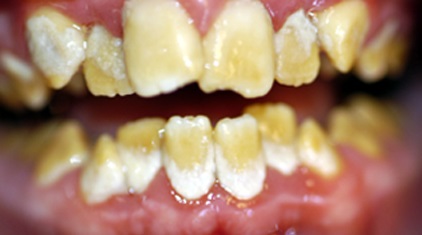

4.2. Anomalie de la dentine

C’est la dentinogénèse imparfaite

, qui était décrite sous le nom de Dysplasie de Capdepont lors de mes études:

Dentinogénèse imparfaite Uninervité de Rennes 1).

Dentinogénèse imparfaite (Uninervité de Rennes 1).